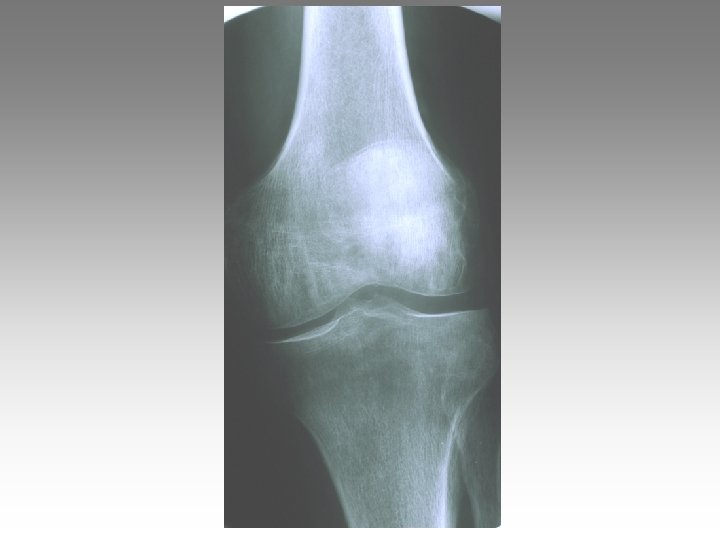

Face debout Schuss Face debout extension Intérêt du cliché de face en position Schuss